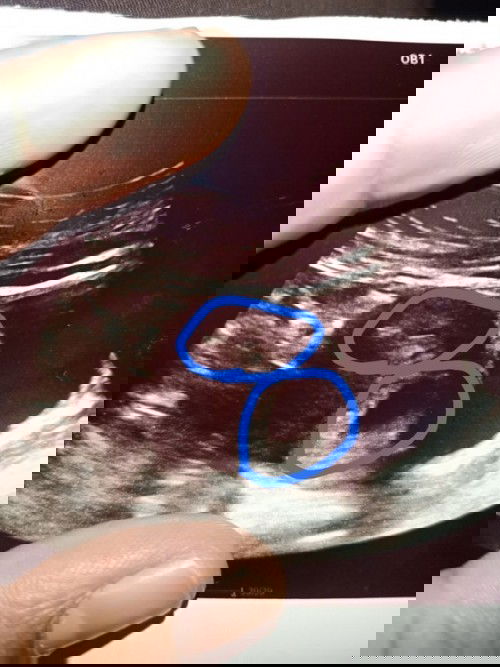

Selamat ptg semua ☺️ kite bru 8 week td sje la g swasta scan .. doc kata twin tp die pon cm ye ke x ,die ckp mcm nmpk 2 kntung ,,yeke ?? πŸ˜…πŸ˜… yg atas tu xjelas sngt mklom la perut tebal. #Second_Baby

wahh , nampak pon mcm twins jugak ni.. tapi tak pasti la kene tunggu baby besar sikit yee.. taniah awak.. kalau baby twins kene double jaga betulΒ² tau banyak risiko.. semoga awak dan baby sihatΒ² dan dipermudahkan segalanya aminn..

itulah doc pon kata mcm tu ,kna tnggu besar skit bru nmpk ☺️ iyurp betul kna jga btul2 ,insyaallah terima kasih awak πŸ€—πŸ€—amiin2 🀲🏼